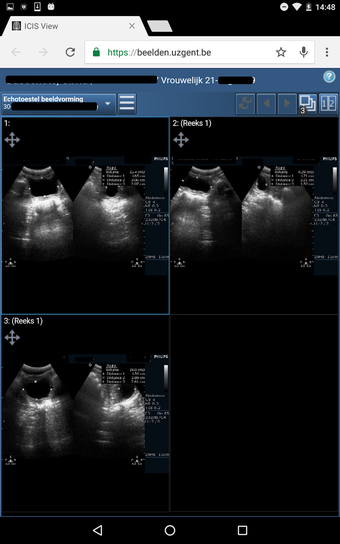

CoZo permet aux patients de prendre une part active dans leur propre santé et d'être traités comme des participants actifs dans le processus de soins. Les patients peuvent utiliser l'application pour enregistrer leurs données de santé, qu'ils peuvent ensuite partager avec leurs médecins. Les médecins peuvent utiliser l'application pour enregistrer l'historique médical de leurs patients, poser un diagnostic et suggérer un plan de traitement.